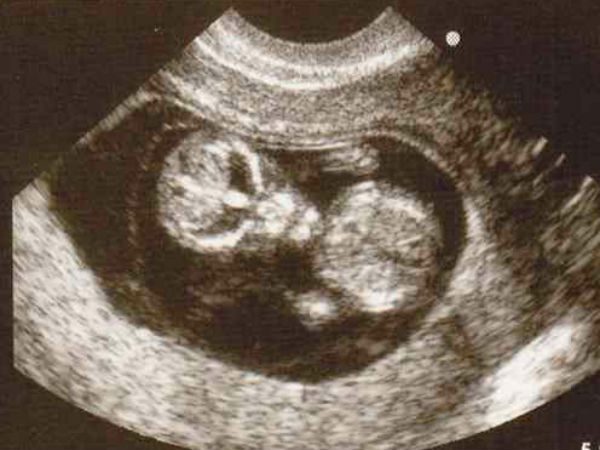

చిత్రం #1 గ్రహాంతర శిశువు!

ఈ బిడ్డ నిజంగానే గ్రహాంతర వాసి లా కనిపిస్తున్నాడా లేదా నిజమైన గ్రహాంతర శిశువా? సరే, ఇది నిజమైన బిడ్డ బైటికి వచ్చే సమయం మాత్రమే! మేము శాంతి వస్తుందని ఆశిస్తున్నాము. ఒకసారి ఆ కుటుంబం చిత్రంలోని విచిత్ర౦గా ఉందని గ్రహిస్తే, అది గొడవలకు దారితీస్తుంది!